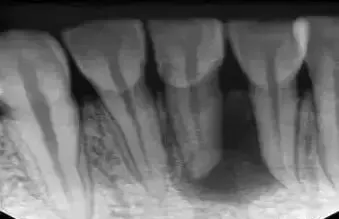

术前拍摄X线片

在根管治疗过程中,在根管治疗术前拍X线片,可以帮助诊断,了解髓室的位置和根管数目及形态,测量根管工作长度。